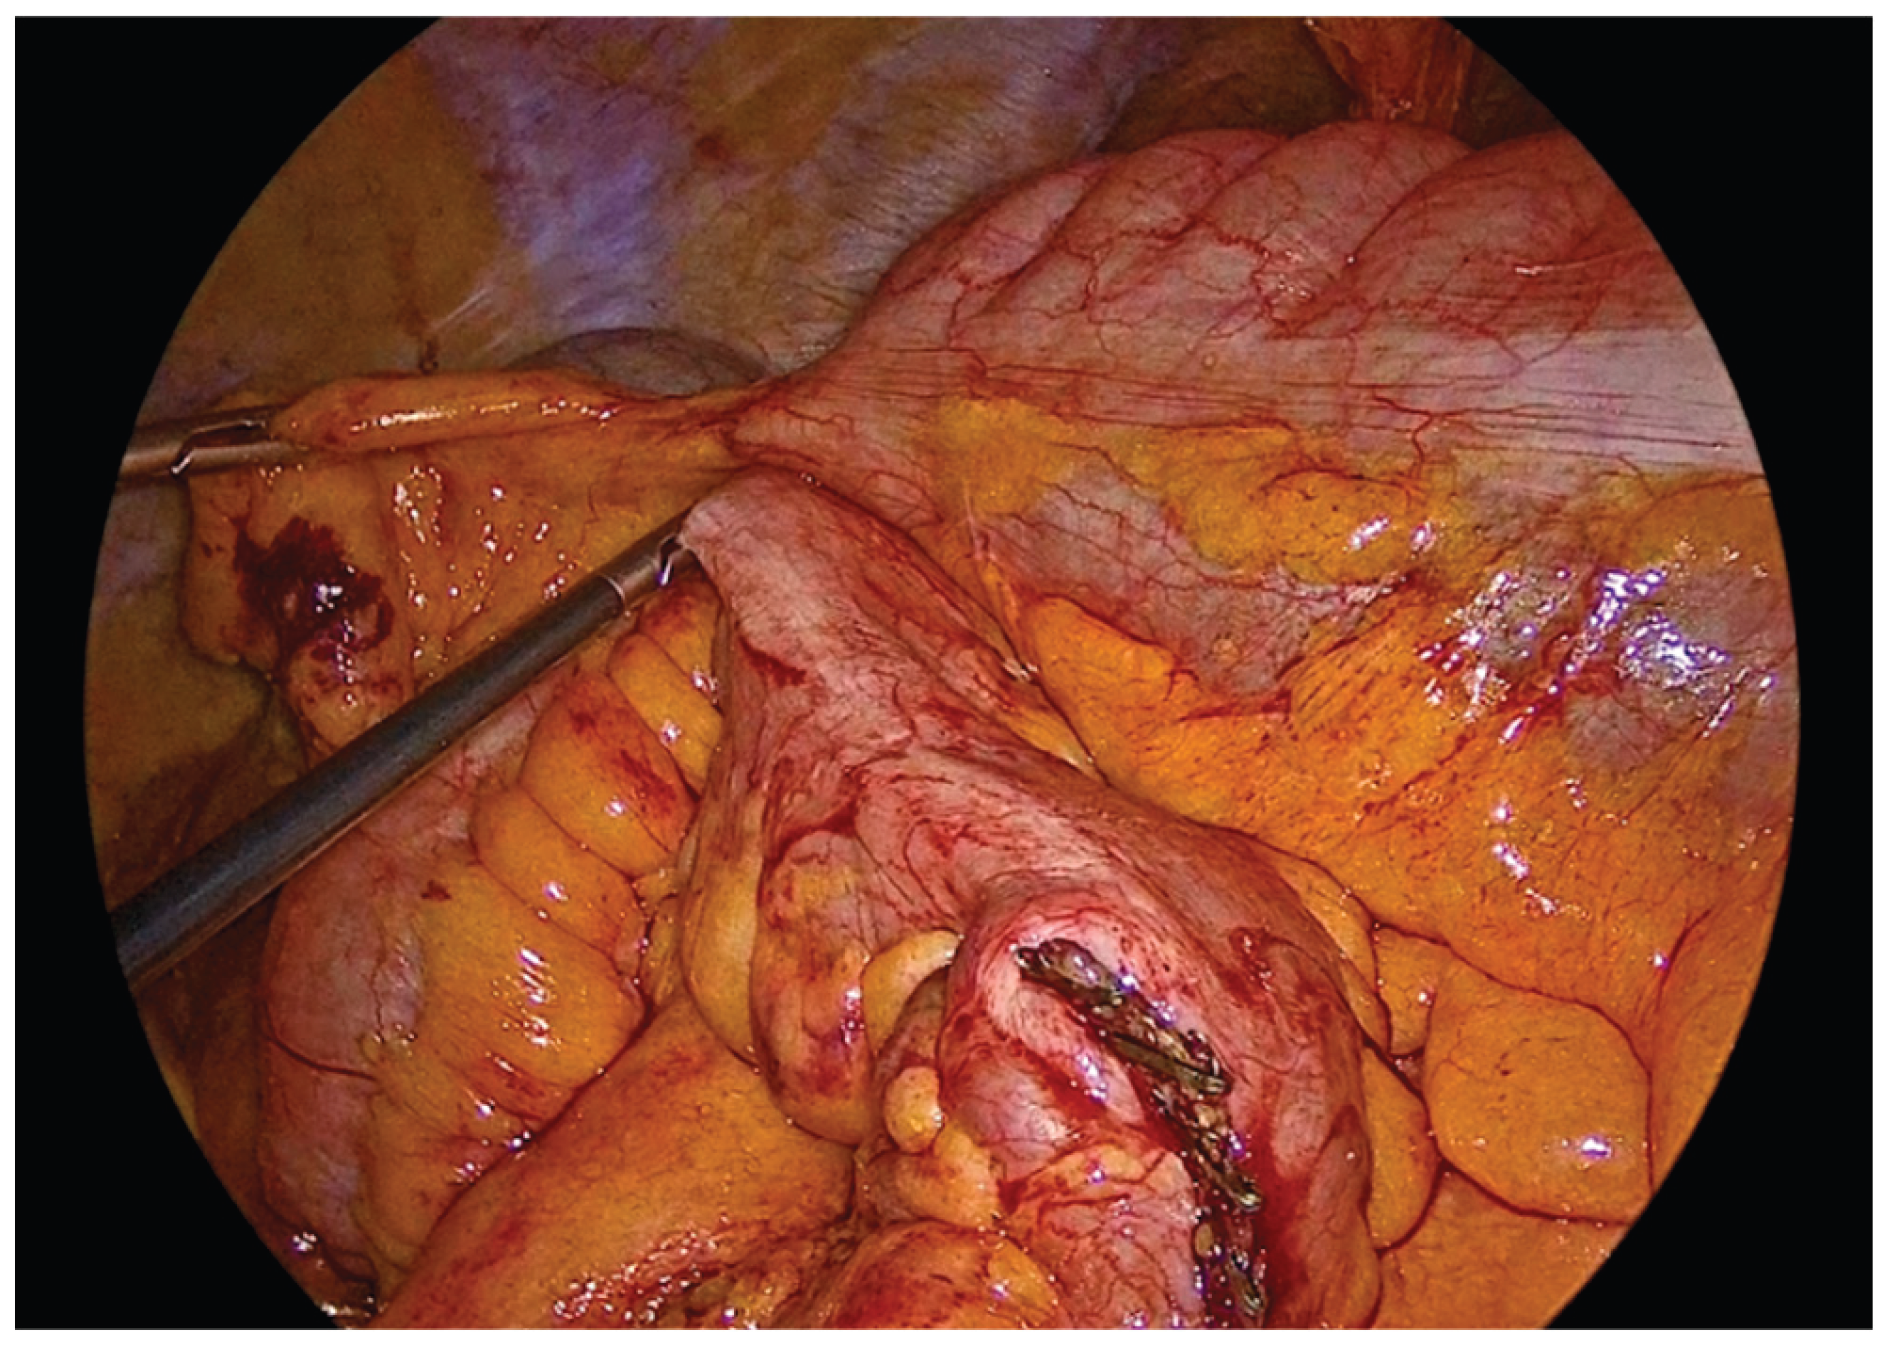

Following complete mobilization of the specimen and the transection of the mesocolon and associated vessels, the terminal ileum and transverse colon are divided using a 60mm endoscopic linear stapler. The specimen is temporarily positioned over the liver to maximize the operative field and facilitate construction of the anastomosis.

The transverse colon and terminal ileum are aligned in an isoperistaltic, side-to-side orientation, approximately 5 cm proximal to the stapled ends using barbed No.3-0 suture 15cm long. A single - layer handsewn intracorporeal anastomosis is then fashioned using a Vicryl No.3-0 suture 34cm long.

Figure 5. Alignment and positioning of the terminal ileum and transverse colon in an isoperistaltic, side-to-side configuration.

Preprints 195043 g005